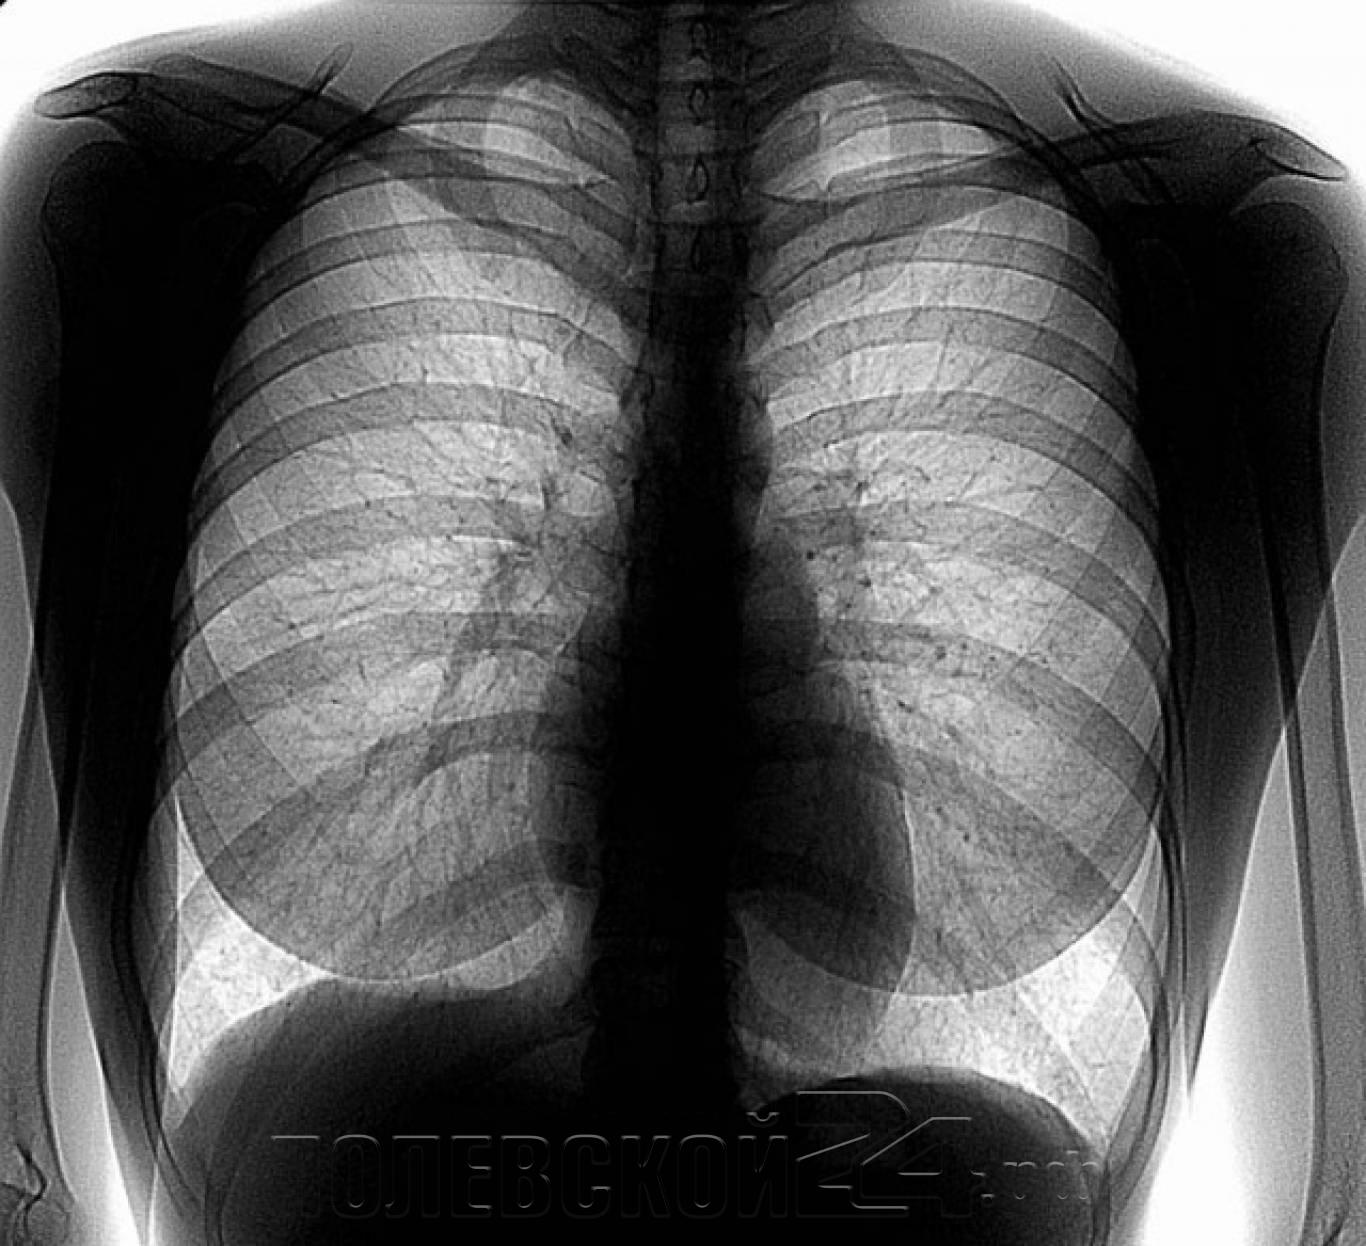

Жители полевских сел и поселков, пройдите флюорографию! К вам приедут!

Для жителей сел и поселков Полевского с 24 июня по 4 июля 2024 года идет профилактическое флюорографическое обследование с помощью передвижной флюорографической

установки.